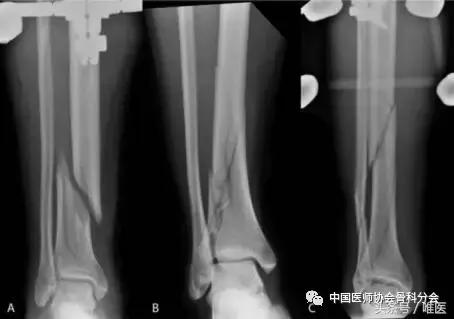

多项研究已经描述了胫骨远端简单关节内骨折的治疗。Robinson等报道了63例胫骨远端骨折,其中20例骨折线延伸到踝关节,伴有内踝或后踝骨折。7例患者在进行胫骨骨折髓内钉固定的同时,对移位的踝部骨折块使用松质骨螺钉固定。踝关节骨折与临床或放射性并发症没有相关性。(图1)

图1:3例患者胫骨远端关节内骨折的正位X线片。患者A:30岁的男性,从自行车上掉下来(A)。患者B:21岁男性,与摩托车相撞(B)。患者C:30岁的男性,阳台坠落伤(C)。